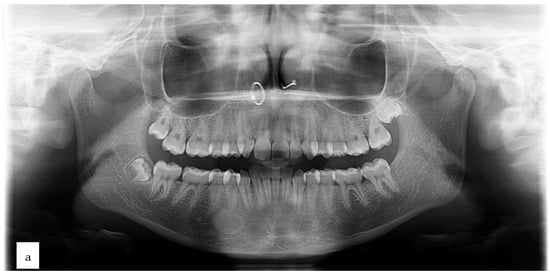

2. Case Presentation